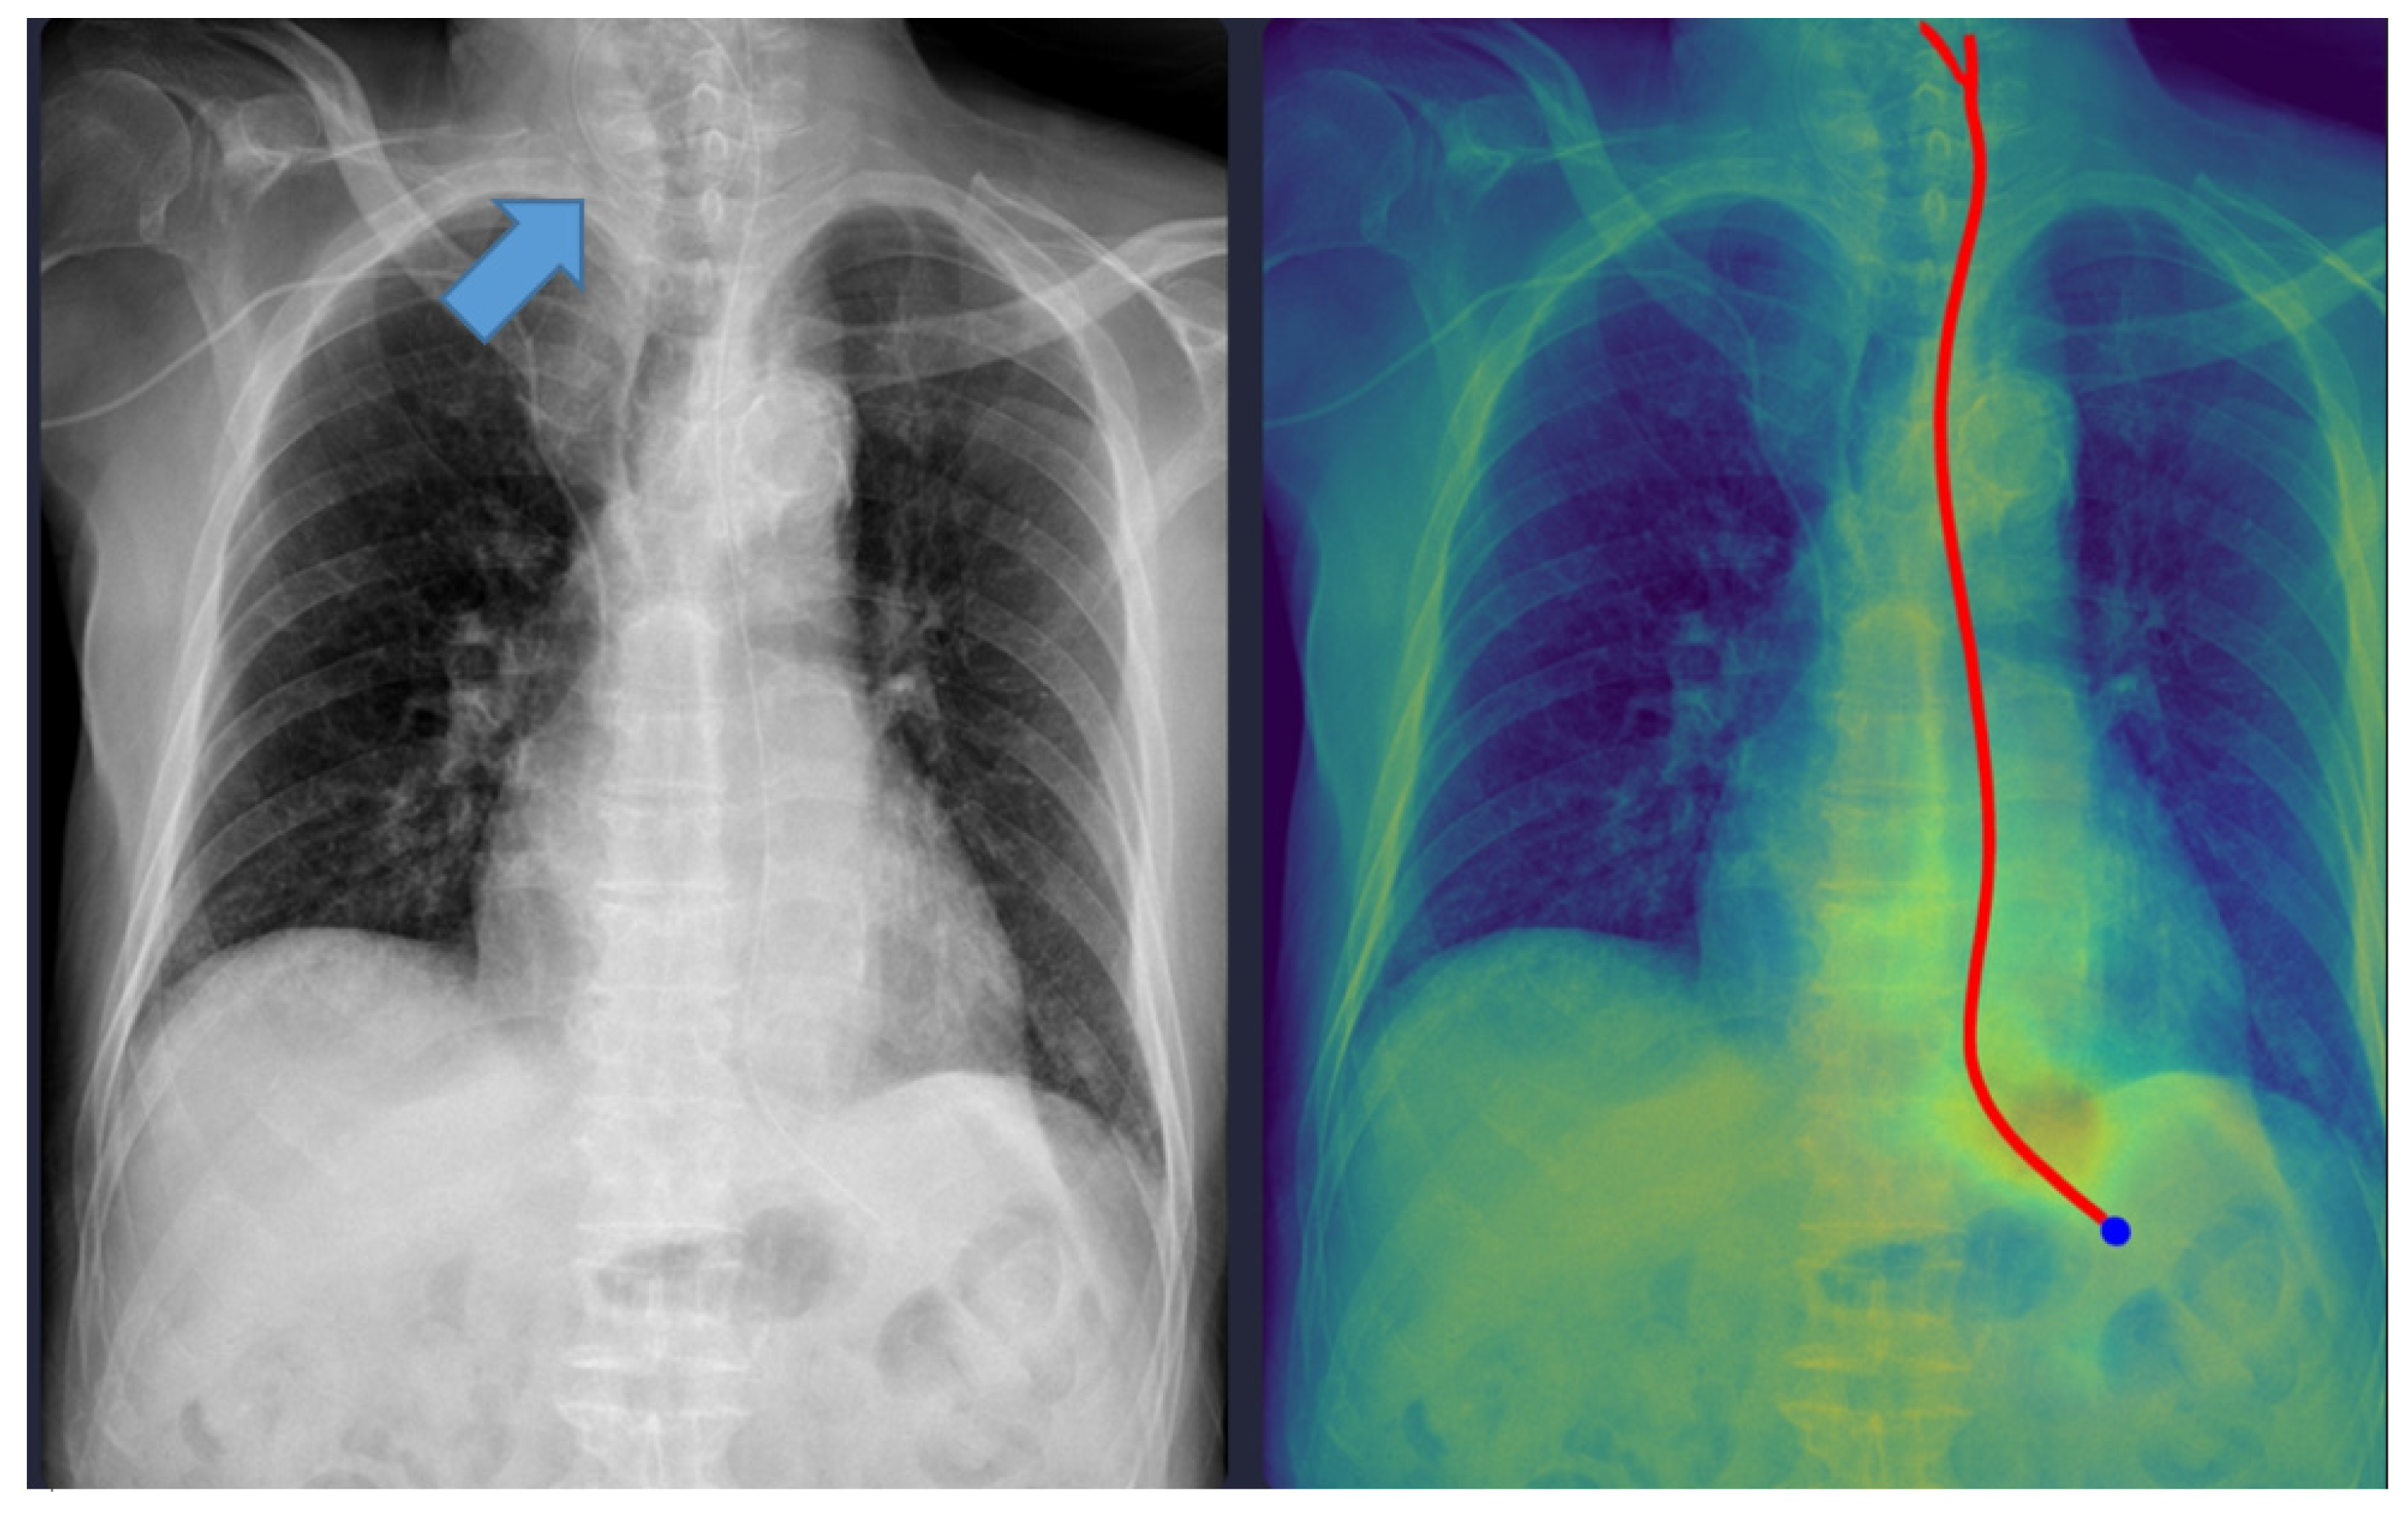

Representative examples of misclassified cases are shown in Figure 2 and Figure 3. The most critical failure involved an NG tube coiled at the indicated site in Figure 2, which suggested incomplete placement and a significant safety risk. The DL model misclassified this case as ‘complete’ based solely on the position of the tip projected below the gastroesophageal junction. Technically, this false-positive classification was highly likely due to the scarcity of such complex, coiled morphological features in the training dataset. While the segmentation module correctly identified the general tube structure, the dual-stage model failed to recognize this pronounced looping or coiling as an immediate risk factor, resulting in the classification module overriding the critical incomplete placement status. This finding identifies a crucial, previously unanticipated failure mode in the model’s design and carries substantial clinical significance, as initiating feeding through a coiled tube presents a high risk of aspiration pneumonia. Moving forward, efforts must focus on incorporating a greater diversity of these rare, yet clinically critical, coiled cases into the dataset to enhance the robustness of the tube segmentation process, thereby ensuring improved and safer clinical implementation. In Figure 3, the DL model failed to draw the entire trajectory of the NG tube and misclassified a complete case as incomplete. A representative example of a correctly classified case is shown in Figure 4. The tip of the NG tube is placed under the gastroesophageal junction and is safe to feed. Because most cases were correctly positioned (=95%), prevalence bias likely inflated the AC1 coefficient, and κ was lower despite near-identical classifications. Future studies should include more incomplete cases to obtain stable reliability estimates [12]. Prevalence-adjusted bias-adjusted kappa (PABAK) estimates were also evaluated with bootstrapping confidence intervals [13]. The results of the agreement among physicians and the DL model are shown in Table 4. Cohen’s κ showed the smallest estimate of 0.644 (95% confidence interval (CI): 0.366–0.922), which increased when using PABAK (0.911 (95% CI: 0.812–0.967)) and Gwet’s AC1 coefficient (0.956 (95% CI: 0.907–0.991)).

4.1. Failure Case Analysis and Safety Implications

Although the physicians agreed in all cases, six cases were discordant between the physicians and the DL model. One case was misclassified as ‘complete’ despite the NG tube being incompletely inserted (coiled), which could have been potentially fatal. As shown in Figure 2, the model interpreted it as complete because the tip of the NG tube was projected below the gastroesophageal junction level. The standalone Gradient-weighted Class Activation Mapping (Grad-CAM)-based heatmap and standalone segmentation-derived probability map are shown separately in Supplementary Figure S1. This figure demonstrates the interpretability of our model, which provides images of both maps overlaid together.

Figure 2. A misclassified incomplete nasogastric tube case identified as complete by the model. The arrow indicates the coiled portion of the nasogastric tube. The red line represents the trajectory of the nasogastric tube, and the blue dot indicates the tip of the nasogastric tube as identified by the deep learning model.